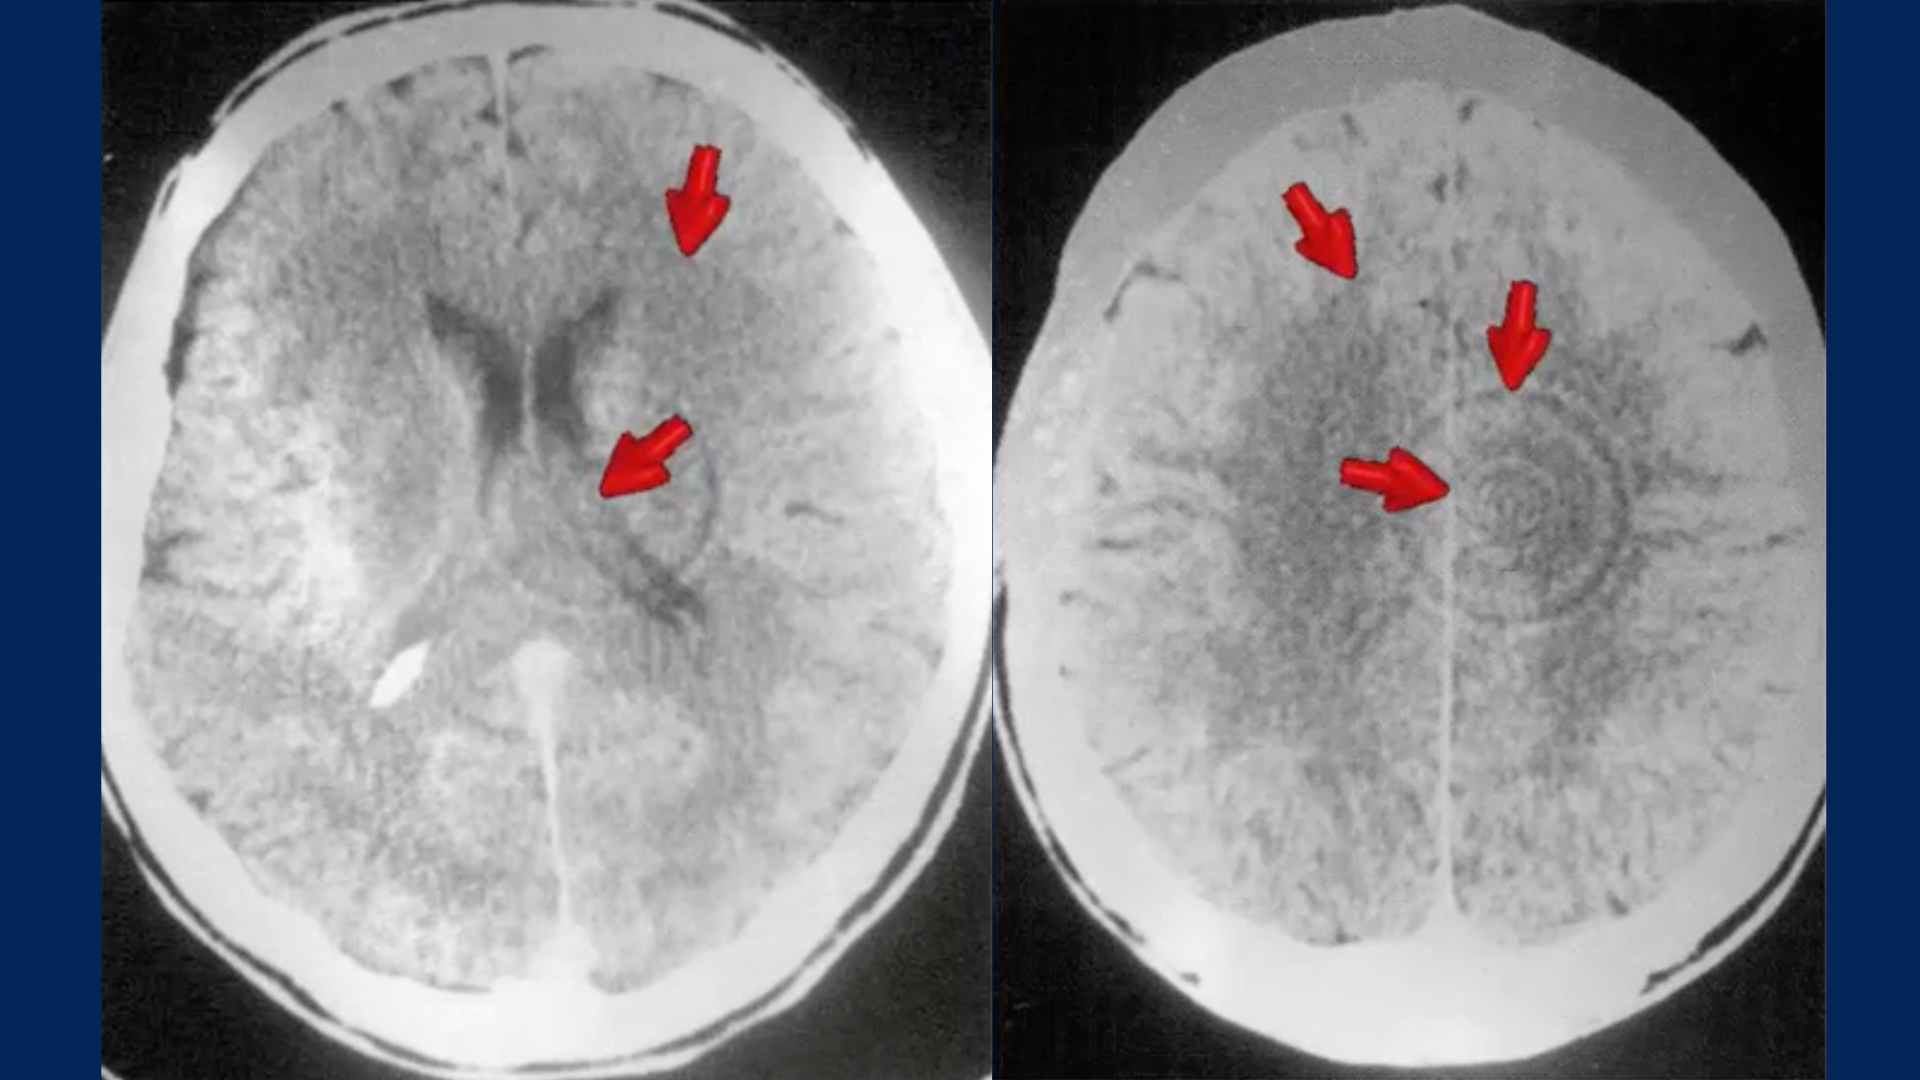

Integrating the pivotal role of the brain, specifically the Hamer Herd (HH), into our understanding of German New Medicine (GNM) deepens our appreciation for the body’s holistic and interconnected nature. The HH, as observed through brain CT scans, represents the precise brain location corresponding to the biological conflict experienced by the psyche. This discovery underscores the brain’s central role in initiating and guiding the body’s response to the acute emotional distress, manifesting intelligent changes in the correlated organ.

In the context of GNM, the HH’s significance cannot be overstated. It serves as the control center that directs the body’s biological programs in response to specific emotional-biological conflicts. When an individual experiences a distressing event or unexpected conflict shock (DHS), the brain relay corresponding to that specific emotional theme becomes active with an HH. This activity is manifested by concentric rings on a CT scan, a direct indicator of the brain’s mediation of the body’s adaptive response to the psyche’s experience.